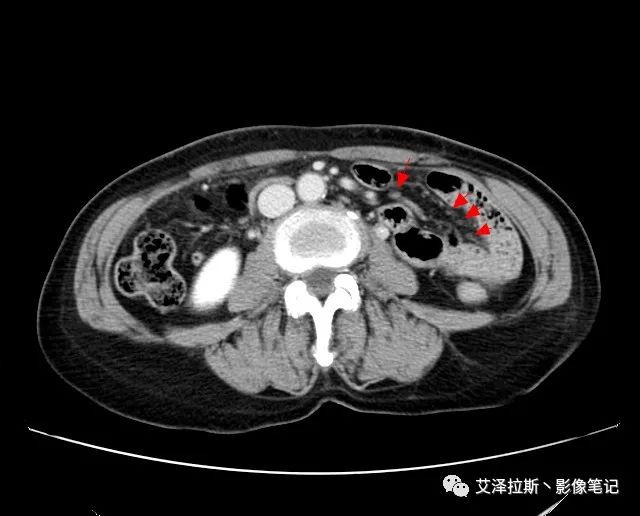

以下為累及的區域淋巴結,共計15個區域:

【影像所見】 胃竇部狹窄,胃壁環形增厚,小彎側見一巨大潰瘍,周圍伴“環堤征”,漿膜面不完整,胃周脂肪見網格狀條索影,病灶與肝臟左葉、胰腺鉤突脂肪間隙消失,增強掃描病灶明顯強化。引流區內約15個區域淋巴結受累。

【診斷意見】 胃竇部胃癌(T4N3期) 該病例腫塊突破漿膜層,與肝臟左葉、胰腺鉤突分界不清,脂肪界面消失,定為T4期; 受累及的淋巴結為15個區域,定為N3; 有無遠處轉移尚不明確,所以M期暫時無法確定。